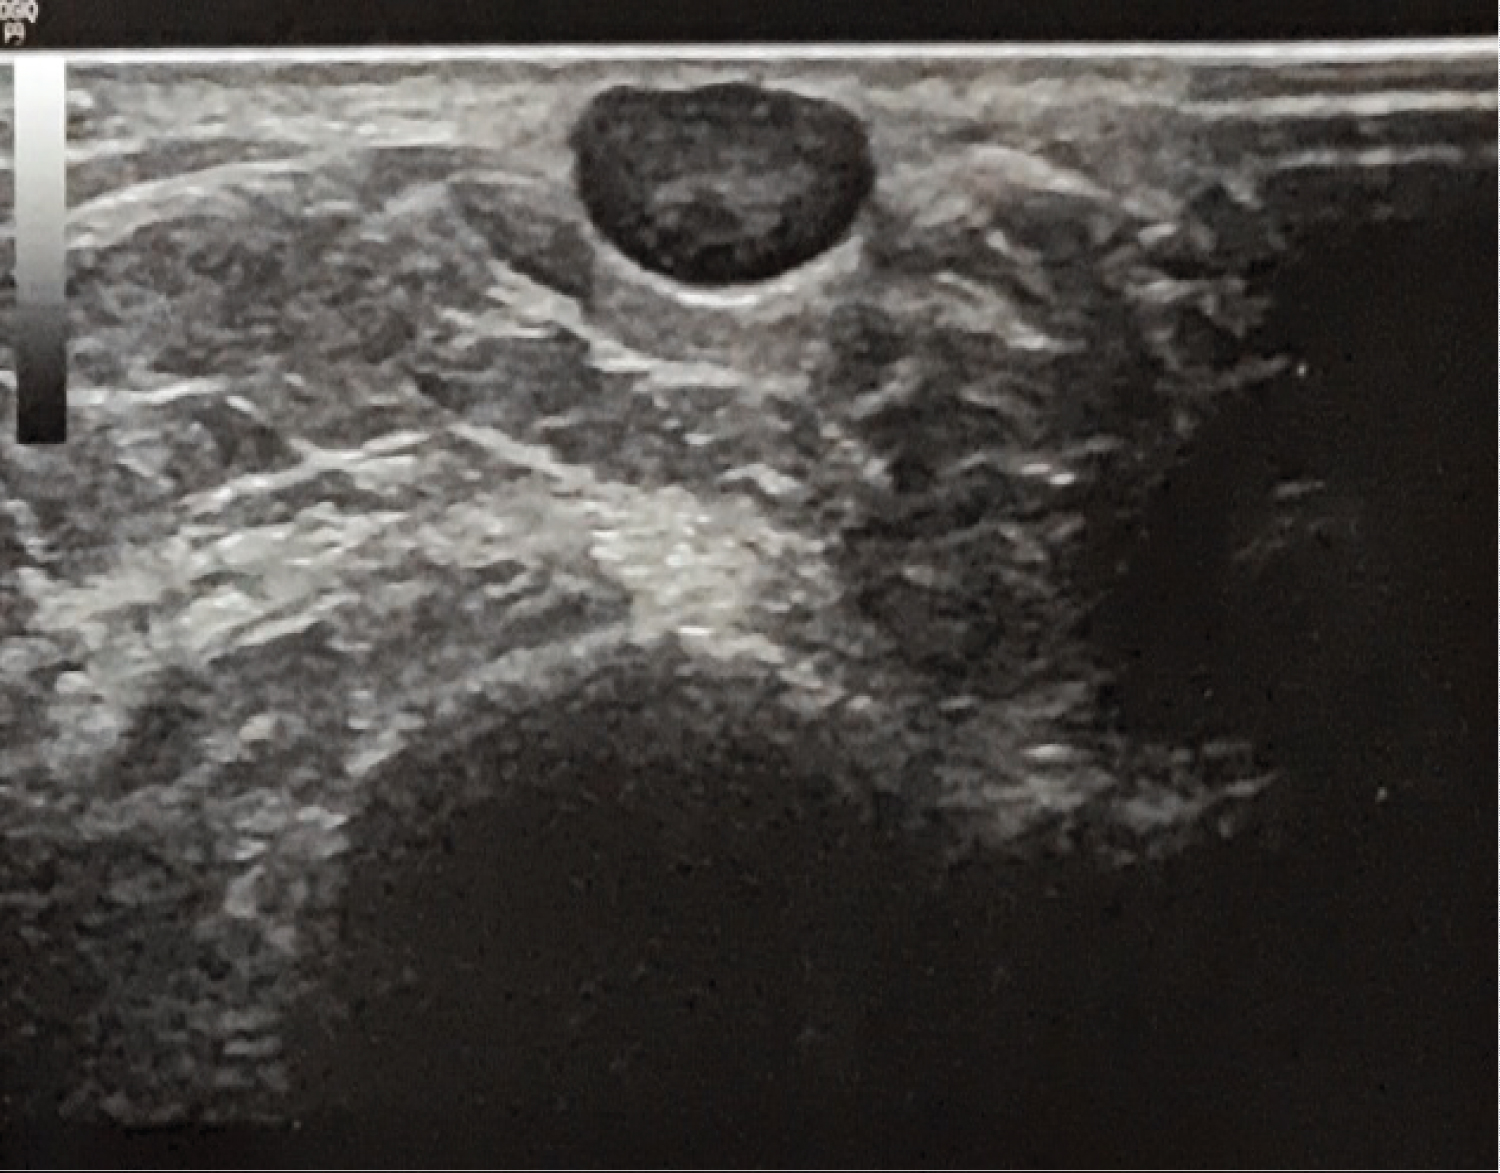

Ultrasounds results shows well-limited superficial ovoid subcutaneous nodule of the external side of the left ankle without septa or intralesional necrosis, hypervascularized by colour Doppler, evoking in first place a schwannoma (Figure 2 and Figure 3).

Figure 2: Subcutaneous ovoid structure with sharp and regular contours. Slightly heterogeneous hypoechoic aspect. View Figure 2